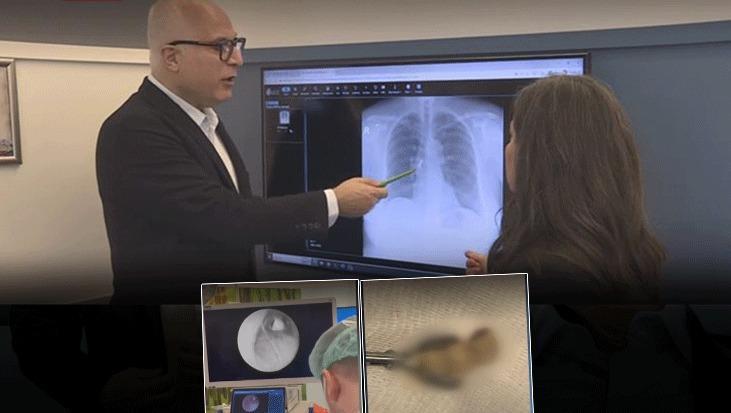

Göğüs Hastalıkları Uzmanı Prof. Dr. Levent Alpay, akciğer filminde üç dişten oluşan kaplama köprüsünün aspire edildiğini fark ettiklerini ve hastayı hemen yatırdıklarını söyledi. Sabah uyandığında dişlerinin yerinde olmadığını gören hastanın, dişleri yutmuş olabileceğini düşündüğünü belirten Alpay, bu tür durumlarda genellikle mideye kaçma ihtimalinin daha yüksek olduğunu vurguladı.

TRT Haber’e konuşan Göğüs hastalıkları uzmanı Prof. Dr. Levent Alpay’ın açıklamaları şöyle;

“Çekilen akciğer filminde kaplama dişin üç dişten oluşan kısmının aspire edildiğini görerek hastamızı hemen yatırdık. Sabah uyandığında dişlerinin ağzında olmadığını gören hasta, “Acaba yuttum mu?” diye düşündü. Genelde bu tür durumlarda yutma söz konusu olur.